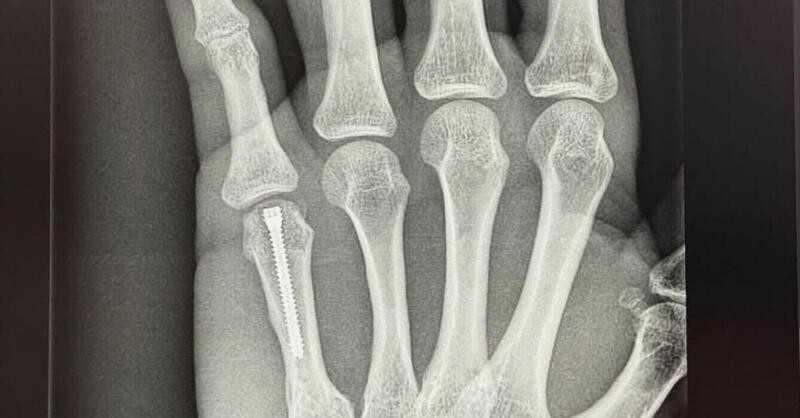

Dopo l’incidente durante i test di Sepang, Jorge Martin ha condiviso sui suoi social i progressi della riabilitazione, mostrando la sua grande determinazione per tornare presto a correre. Il pilota spagnolo, Campione del Mondo Moto3 nel 2018 e MotoGp nel 2024, ha sempre dimostrato grande tenacia, superando infortuni e sfide in pista.

Martin, attualmente è tra gli interpreti più illustri della MotoGP con il team ufficiale Aprilia e nonostante un avvio di campionato decisamente sfortunato è al lavoro per recuperare al più presto. Le immagini della sua riabilitazione, pubblicate online, hanno galvanizzato i fan. Con la sua grinta e il sostegno del team, il ritorno in pista sembra solo questione di tempo, forse già dal GP della Tailandia